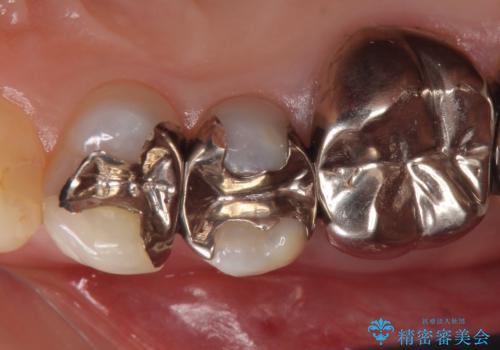

- 右上5番目の歯がなにもしなくてもズキズキ痛むので診て欲しいといらっしゃった方の症例です。

診査の結果神経を保存するのは困難だったため、根管治療を行った後、オールセラミッククラウンによる補綴を行いました。